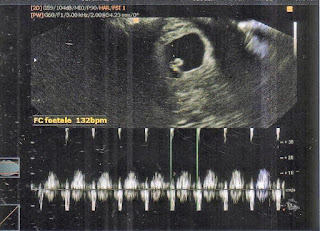

Le 25 novembre 2011, j'ai fait une écho de contrôle.

Pour voir si j'avais bien réagi.

Comment était mon endomètre, si j'avais des kystes plus gros etc...

Mais au lieu de cela...

Le plus beau cadeau de ma vie...

Cela fait 4 ans, ce soir à 19h... et ça a mis fin à 8 ans d'infertilité et de souffrances.